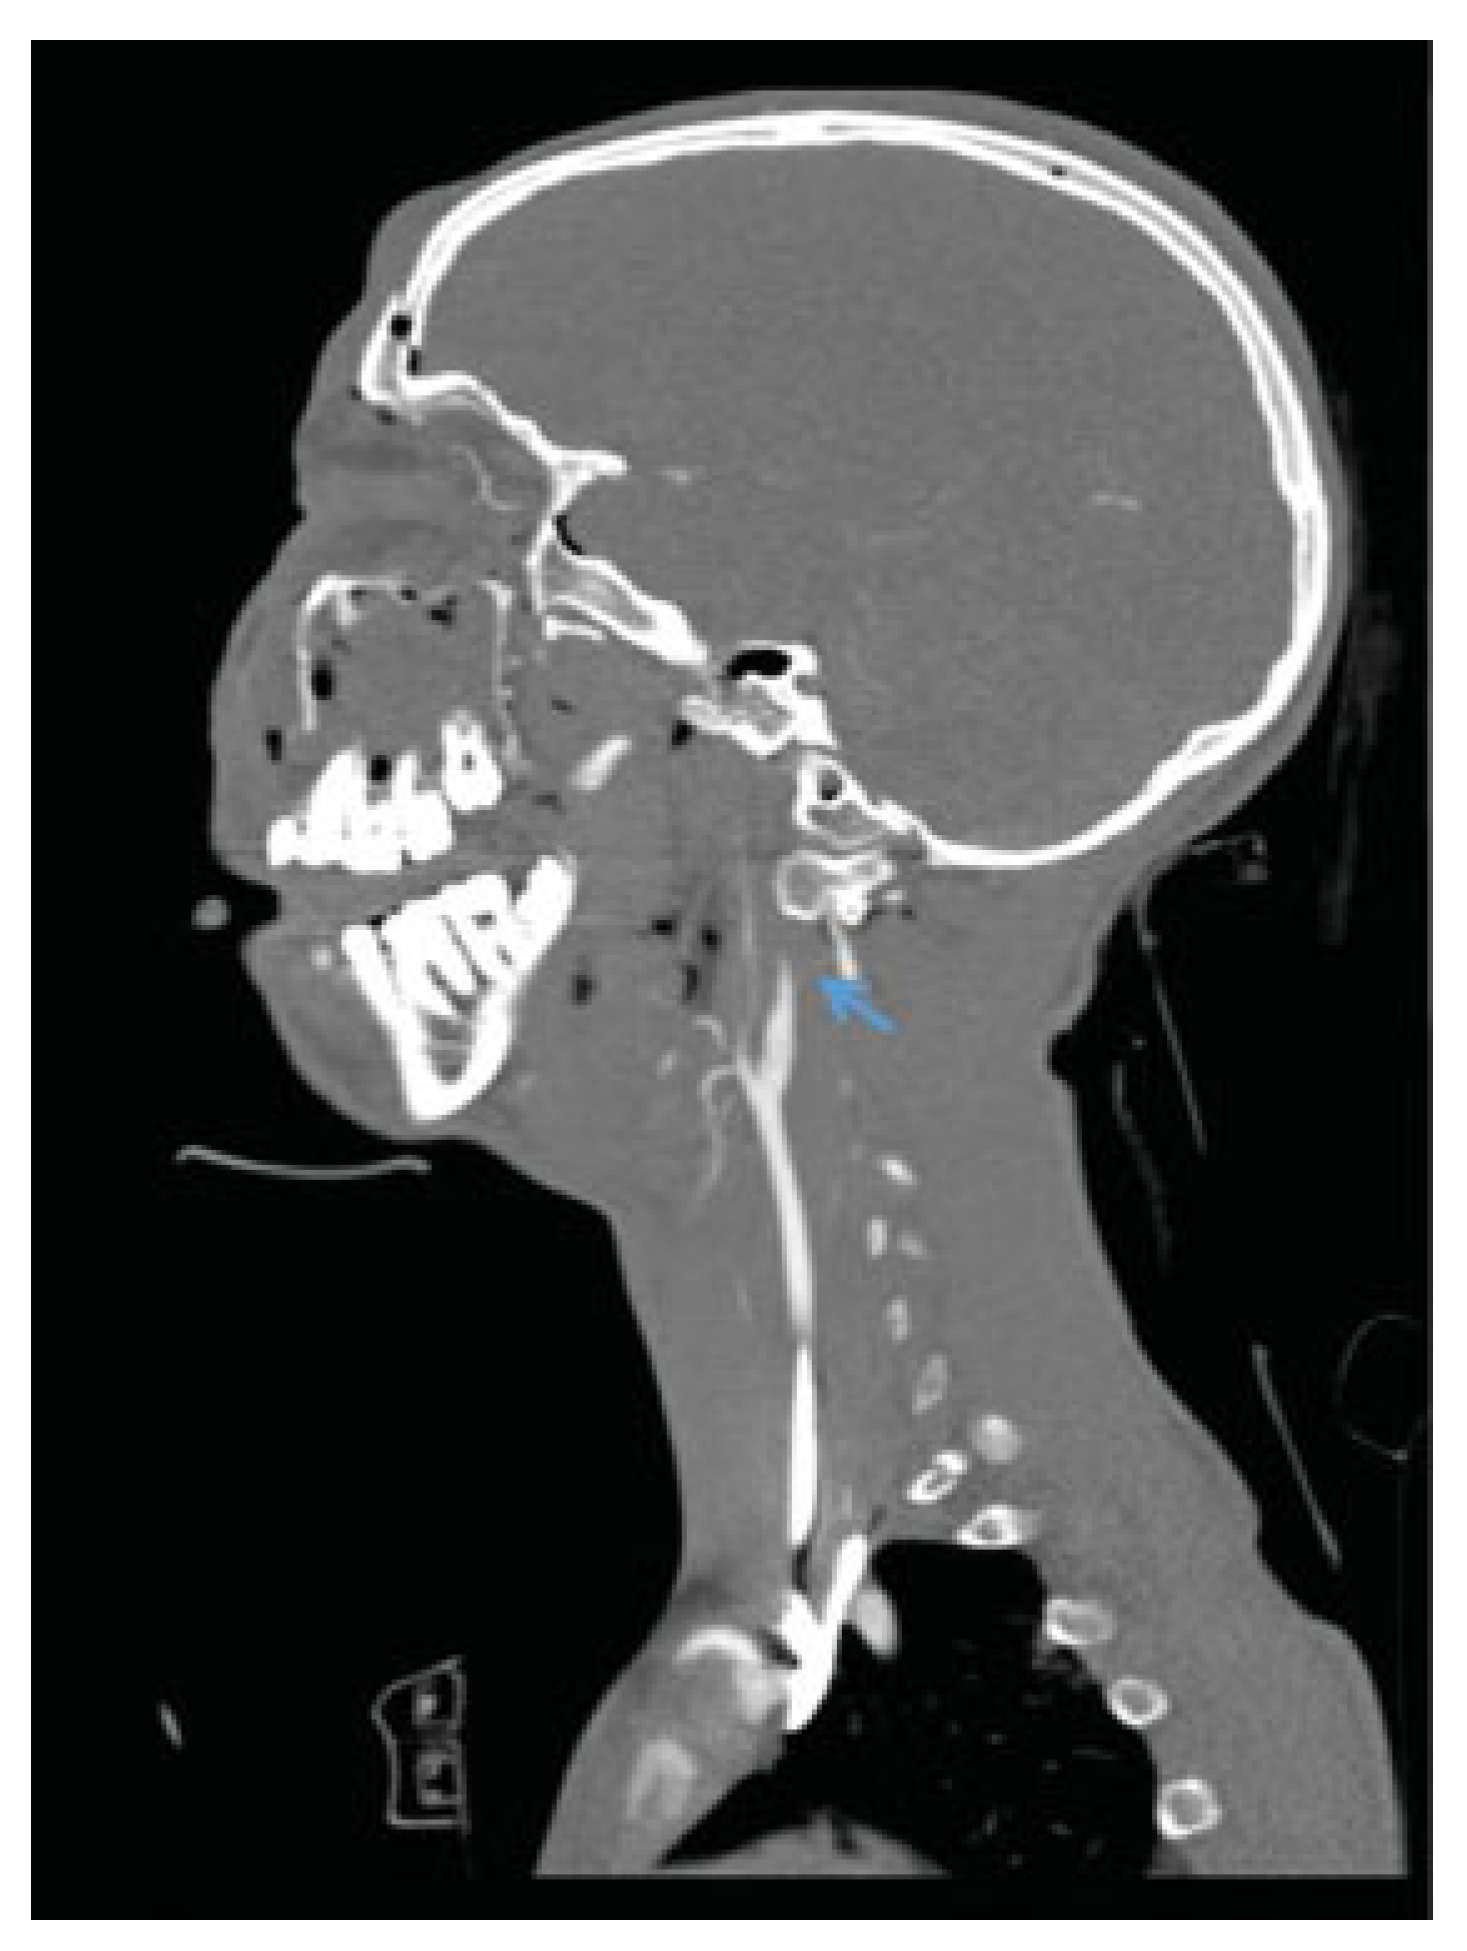

Penetrating Extracranial Carotid Artery Trauma

Intracranial Carotid Artery Trauma